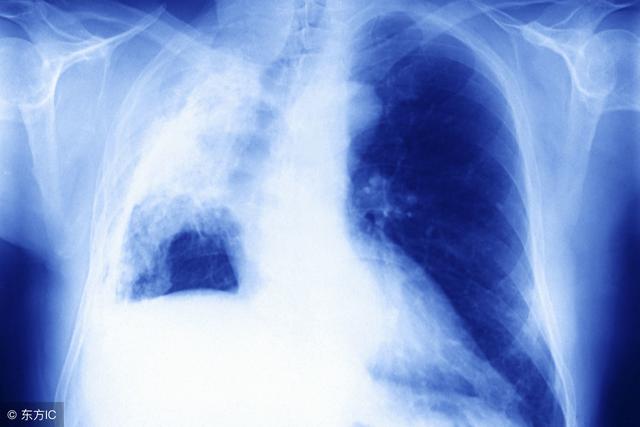

典型病例72岁健康爷爷患“蜂窝肺”手指头变得像肉球今年72岁的张爷爷是一体育爱好者平时有空还到处旅游虽已七旬,但连感冒都很少有可从去年底开始他感觉自己的身体有些不舒服“好好的干咳起来,上楼,出去买个菜,就气喘,晚上睡觉也感到呼吸不畅”。

发病原因大多和人们不良的生活习惯有关,尤其是吸烟。除此之外就是空气污染,长时间处于有害的环境之下,如粉尘、汽车尾气、结核杆菌导致肺部出现疾病。